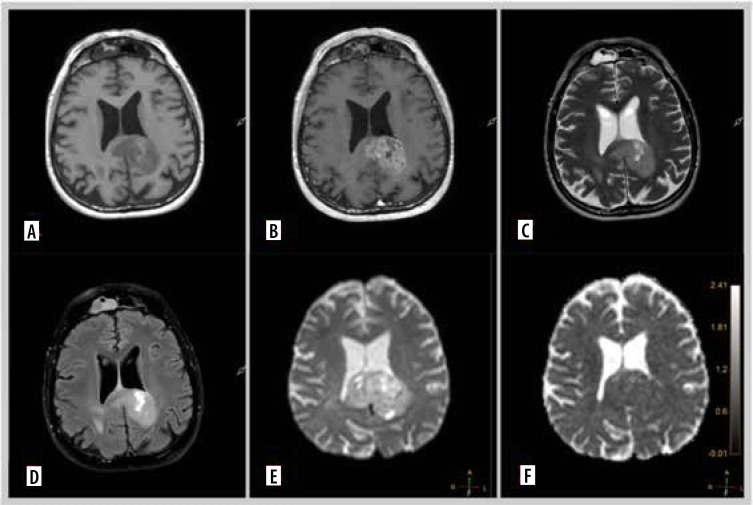

Material and methods: A total of 91 glioma patients treated between August 2023 and March 2024 were included in the analysis. All patients underwent preoperative magnetic resonance imaging (MRI), including DWI, and had available histopathological and genetic test results. Clinical data, tumour characteristics, and genetic markers such as IDH1 mutation, MGMT promoter methylation, EGFR amplification, TERT pathogenic variant, and CDKN2A deletion were collected. Statistical analysis was performed to identify correlations between ADC values, MRI perfusion parameters, and genetic characteristics.

Results: Significant associations were found between lower ADC values and aggressive tumour features, including IDH1-wildtype, MGMT unmethylated status, TERT pathogenic variant, and EGFR amplification. Additionally, distinct ADC patterns were observed in gliomas with CDKN2A, TP53, and PTEN gene deletions. These findings were further supported by contrast enhancement and other MRI parameters, indicating their role in tumour characterisation.